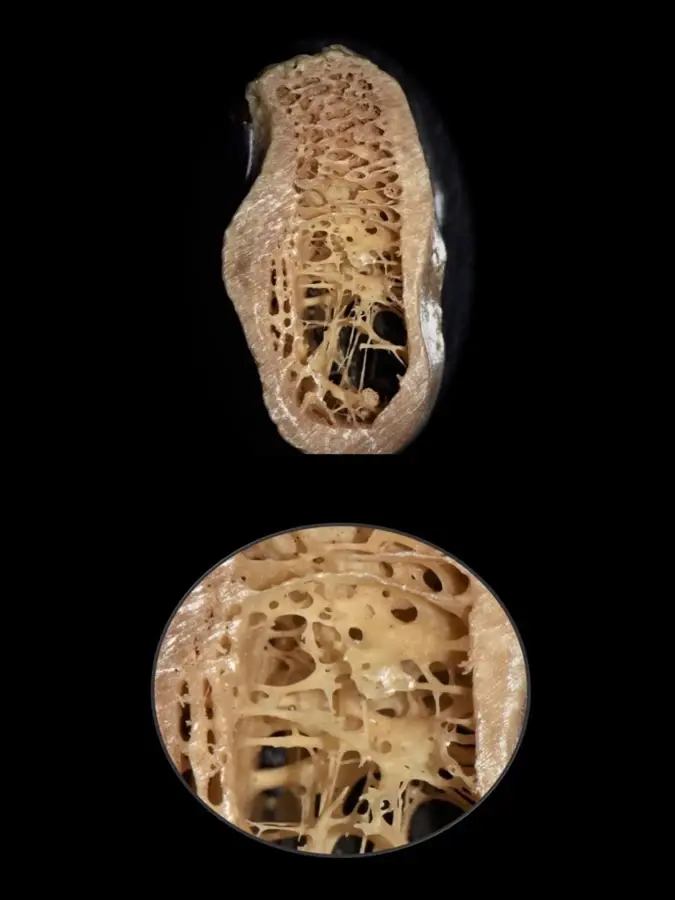

En base a estudios realizados en biomodelos, consideramos que es importante, además de los clásicos parámetros, analizar el grosor de las trabéculas óseas y las dimensiones de los espacios medulares, ya que juegan un rol determinante en la calidad y dureza del hueso.

Las clasificaciones tradicionales asocian la calidad ósea con ciertos sectores en los maxilares

Por ejemplo, se dice que el sector anteroinferior de la mandíbula suele presentarse hueso tipo I y en el posteroinferior tipo II. La variante en la zona posterioinferior mandibular se debe a que, a pesar de tener una buena cortical ósea y cantidad de hueso esponjoso, la dimensión de los espacios medulares es muy amplia y el grosor de las trabéculas tan finas como el espesor de un cabello11 (Figura 3).